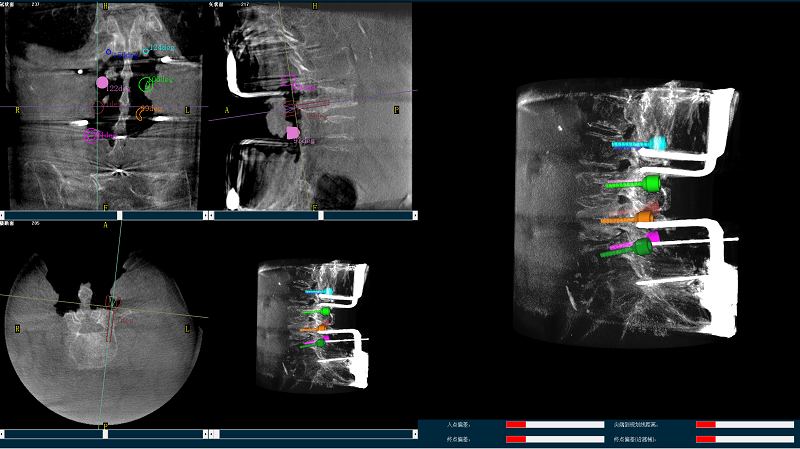

三維圖像

(2)使用普愛醫療平板三維C形臂掃描患者,得到術中三維圖像并傳送至骨科機器人導航系統。骨科機器人導航系統基于高清術中三維圖像進行手術規劃。